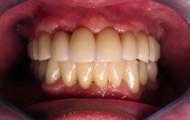

Exemple d’un implant unitaire pour remplacer une dent antérieure manquante.

Exemple d’une réhabilitation complète implantaire